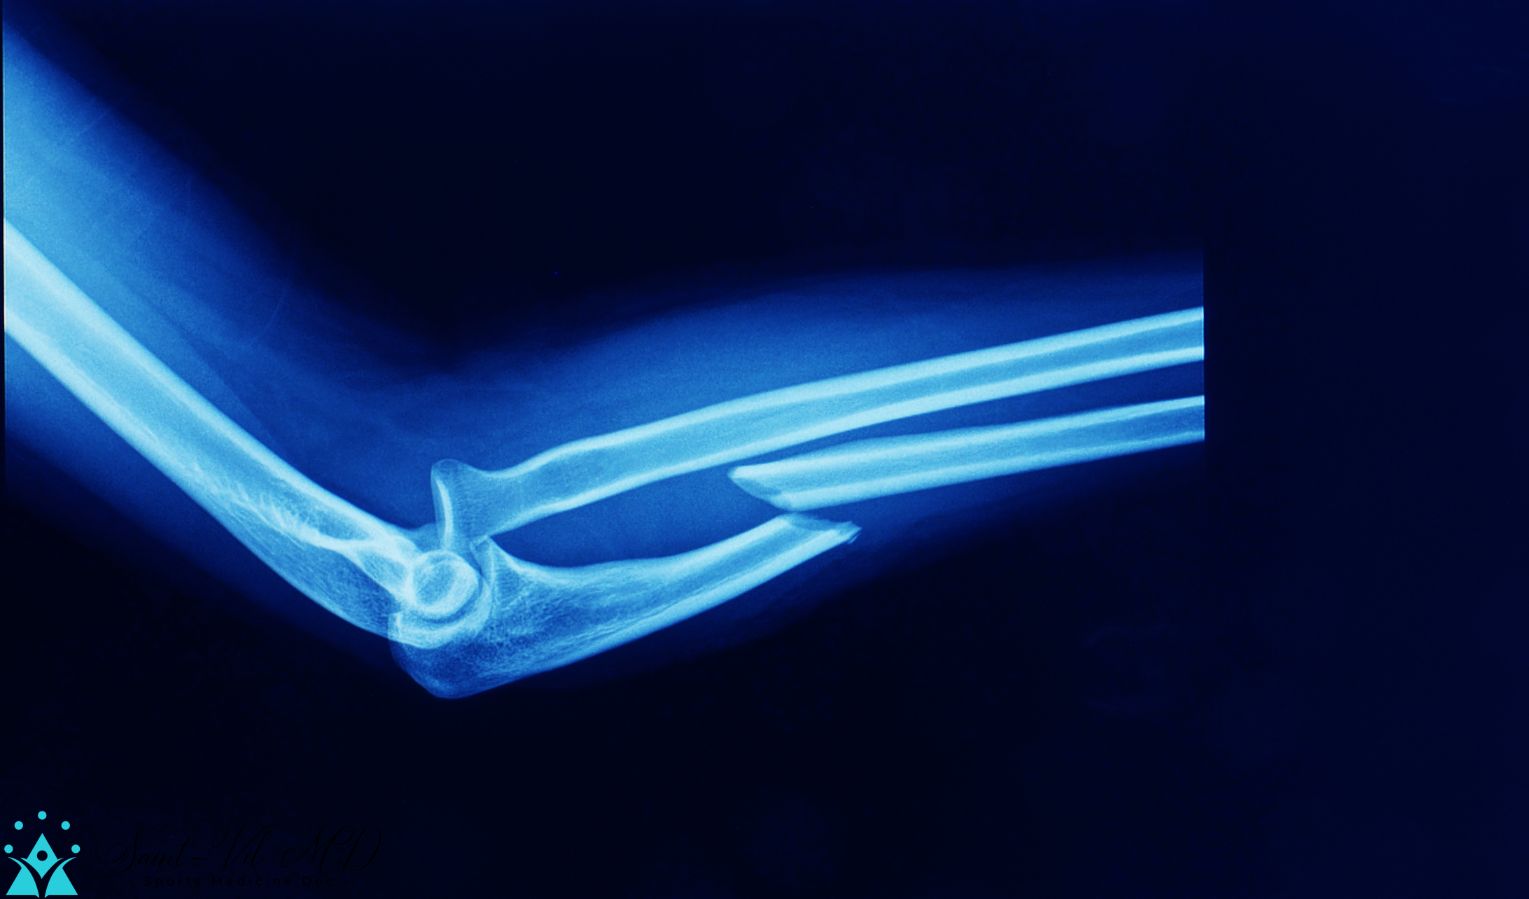

Monteggia Fracture Proximal Ulna Fracture With Radial Head Dislocation Proximal Ulnar Fracture X Ray olecranon fractures are common fractures of the elbow that lead to loss of extensor mechanism. a monteggia fracture is defined as a proximal 1/3 ulna fracture with an associated radial head dislocation. proximal ulna fractures are relatively common upper limb injuries,. also known as a nightstick fracture. Diagnosis can be made with plain. radius and. Proximal Ulnar Fracture X Ray.

Xray of a proximal ulnar fracture with radial head dislocation, known Proximal Ulnar Fracture X Ray fractures of the proximal ulna range from simple olecranon fractures to complex monteggia fractures or. olecranon fractures are common fractures of the elbow that lead to loss of extensor mechanism. Diagnosis can be made with plain. proximal ulna fractures are relatively common upper limb injuries, which may represent fragility fractures or result. radius and ulnar shaft. Proximal Ulnar Fracture X Ray.

Xray Elbow Showing Fracture Proximal Ulna Or Olecranon Fracture Proximal Ulnar Fracture X Ray fractures of the proximal ulna range from simple olecranon fractures to complex monteggia fractures or. olecranon fractures are common fractures of the elbow that lead to loss of extensor mechanism. a monteggia fracture is defined as a proximal 1/3 ulna fracture with an associated radial head dislocation. also known as a nightstick fracture. proximal ulna. Proximal Ulnar Fracture X Ray.

Xray Elbow Showing Fracture Proximal Ulna Or Olecranon Fracture Proximal Ulnar Fracture X Ray a monteggia fracture is defined as a proximal 1/3 ulna fracture with an associated radial head dislocation. olecranon fractures are common fractures of the elbow that lead to loss of extensor mechanism. proximal ulna fractures are relatively common upper limb injuries,. Diagnosis is made with forearm and. also known as a nightstick fracture. Characteristic defensive fracture. Proximal Ulnar Fracture X Ray.

lateral xray of elbow showing fracture of proximal ulnar shaft and Proximal Ulnar Fracture X Ray radius and ulnar shaft fractures, also known as adult both bone forearm fractures, are common fractures of the. proximal ulna fractures are relatively common upper limb injuries, which may represent fragility fractures or result. also known as a nightstick fracture. proximal ulna fractures are relatively common upper limb injuries,. a monteggia fracture is defined as. Proximal Ulnar Fracture X Ray.